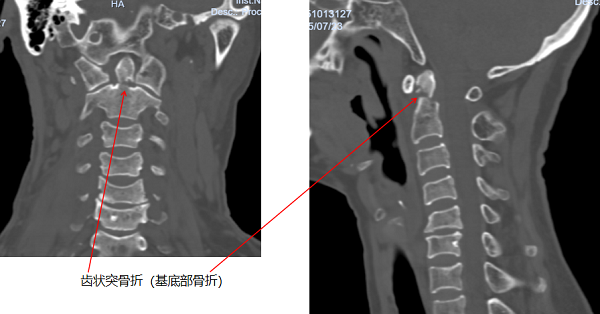

据悉,老奶奶在田间劳作时,不慎从2米高的田埂跌落至沟中,被救护车送至当地医院后,CT检查提示颈椎骨折,随即紧急转入玉溪市人民医院。进一步检查中发现,老人伤情复杂,不仅存在颈椎齿状突骨折、胸腰椎多发骨折、双侧腕关节骨折,还合并头部硬膜外血肿,病情危急。

骨外一科值班医生第一时间启动多学科会诊机制,邀请神经外科、骨外三科专家共同评估病情,围绕患者头部及腕关节外伤制定紧急处理方案,始终坚守“生命第一”的救治原则,快速稳住老人生命体征。待病情平稳后,科室结合骨外三科意见,决定对愈合难度极高的Anderson II型齿状突骨折、第一腰椎骨折实施手术治疗,其余部位采取保守治疗。